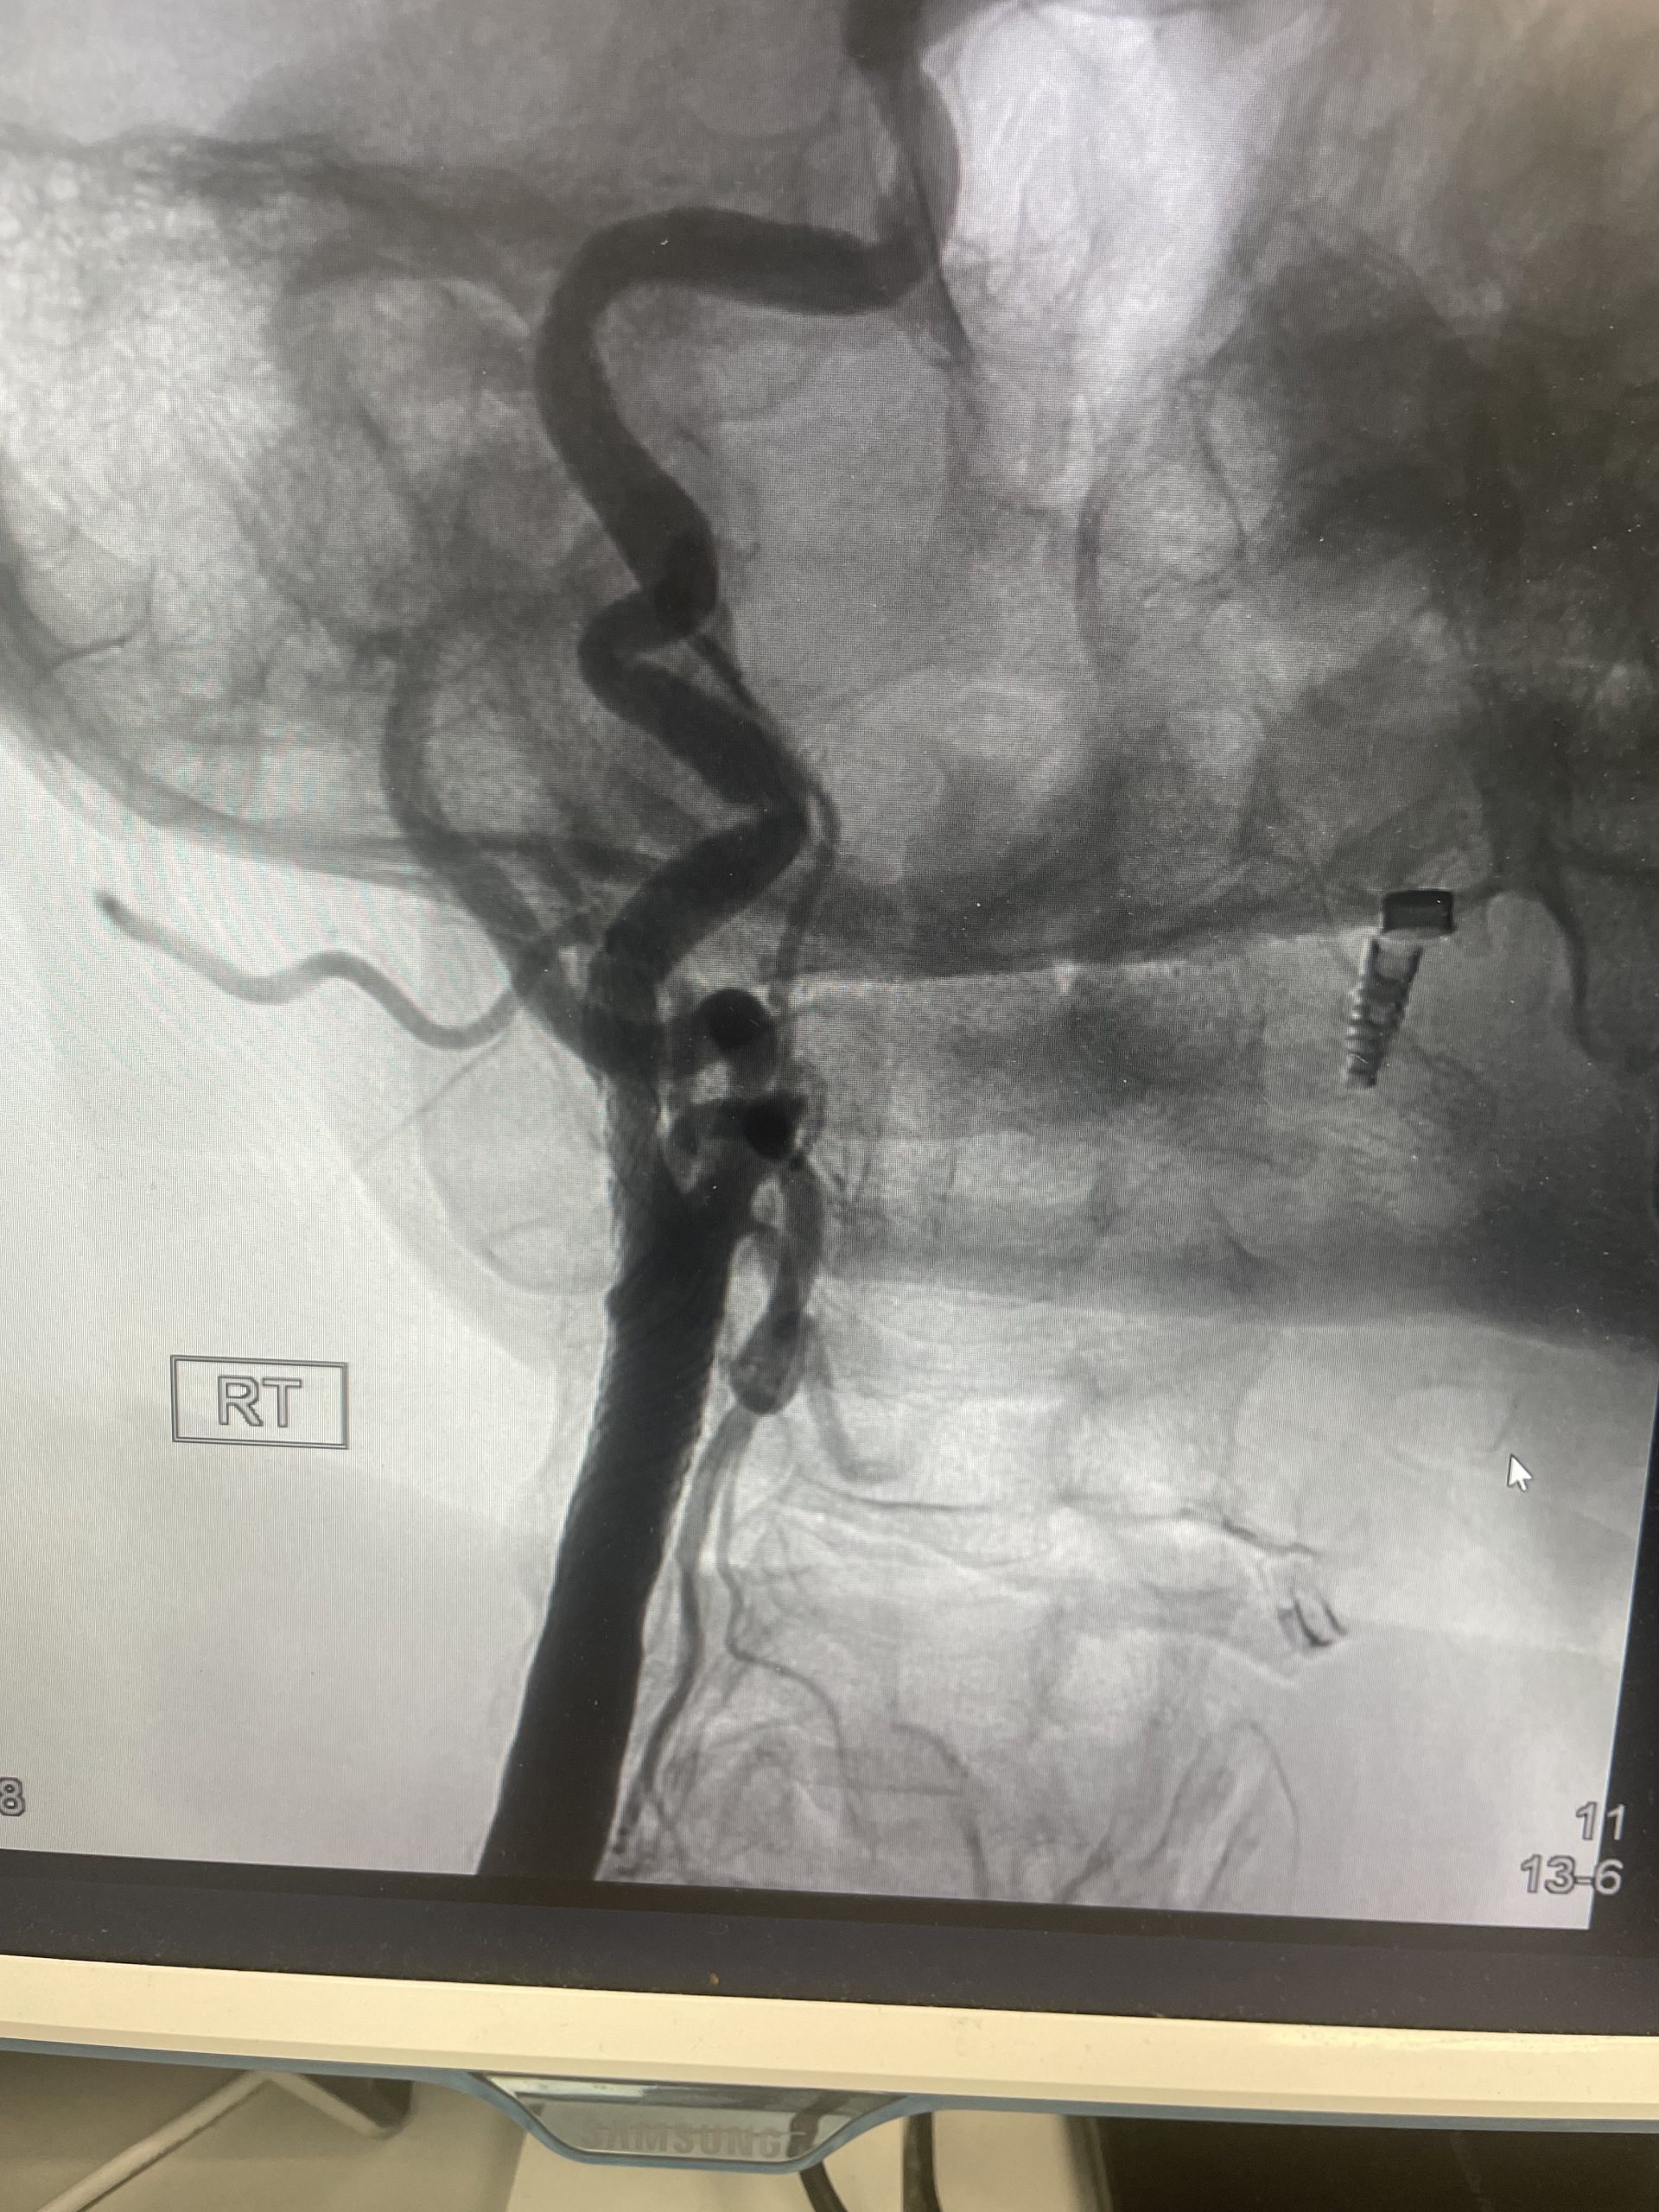

מחקר CREST-2 , מהגדולים והחשובים שבוצעו בתחום מחלות כלי הדם והיצרות עורקי הקרוטיד, פורסם לאחרונה בעיתון הרפואי המוביל NEJM. המחקר מציג תמונה ברורה לגבי הטיפול בחולים שאינם חווים תסמינים מוקדמים (א-סימפטומטיים). התוצאות הראו כי צנתור הקרוטיד עם הנחת סטנט הפחית באופן מובהק את שיעור השבץ לאורך ארבע שנות מעקב. לעומת זאת, בקבוצת הניתוח (אנדארטרקטומיה) לא נמצא יתרון סטטיסטי על פני טיפול רפואי אינטנסיבי בלבד — וגם לא נמצא יתרון על פני סטנט.

היצרות משמעותית של עורקי הצוואר, אפילו כשהיא “שקטה” לחלוטין (ללא סימפטומים), מהווה גורם סיכון מרכזי לשבץ מוחי איסכמי. ניתוח כלי דם (אנדארטרקטומיה) הוא טיפול יעיל ובטוח, שנחשב במשך שנים רבות לסטנדרט המקובל במטופלים מתאימים, ובמיוחד כאשר יש תסמינים. אולם במסגרת CREST-2 , מחקר שבחן במיוחד מטופלים ללא תסמינים ותוך כדי איזון רפואי מיטבי — נראה כי הניתוח לא סיפק תוספת הגנה מעבר לטיפול שמרני בלבד. לעומת זאת, בחולים דומים, צינתור ופתיחה של ההיצרות עם סטנט, תוך שימוש בפילטר המגן מתסחיפים – הציג יתרון ברור וחד משמעי , בהשוואה לטיפול תרופתי מיטבי, ובניגוד לניתוח כלי הדם.

בזרוע הסטנט נמצא יתרון ברור: שיעור האירועים היה נמוך משמעותית לעומת טיפול רפואי בלבד (6% לעומת 2.8%, פער של כ־3%). לעומת זאת, בזרוע הניתוח נרשמה ירידה מתונה יותר בשיעור האירועים, שלא הגיעה למובהקות סטטיסטית (5.3% לעומת 3.7%, פער של כ־1.6%).